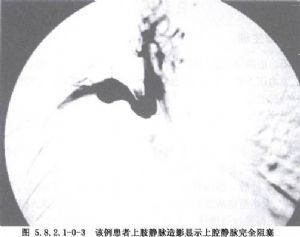

由於大多數上腔靜脈綜合徵是由肺癌引起的,故肺癌的症狀也常見,如氣管或右主支氣管受壓引起的刺激性咳嗽、呼吸困難甚至窒息;膈神經、迷走神經和交感神經受侵犯導致的右膈麻痹、聲音嘶啞、疼痛或Horner綜合徵等(圖5.8.2.1-0-2,5.8.2.1-0-3)。